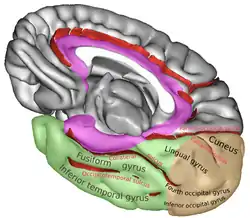

Medial surface of right cerebral hemisphere. (Lingual gyrus visible at right.) | |

The lingual gyrus of the occipital lobe lies between the calcarine sulcus and the posterior part of the collateral sulcus; behind, it reaches the occipital pole; in front, it is continued on to the tentorial surface of the temporal lobe, and joins the parahippocampal gyrus.[3]

Position of lingual gyrus (shown in red).

Position of lingual gyrus (shown in red). Gyri and sulci of occipital and temporal lobe.